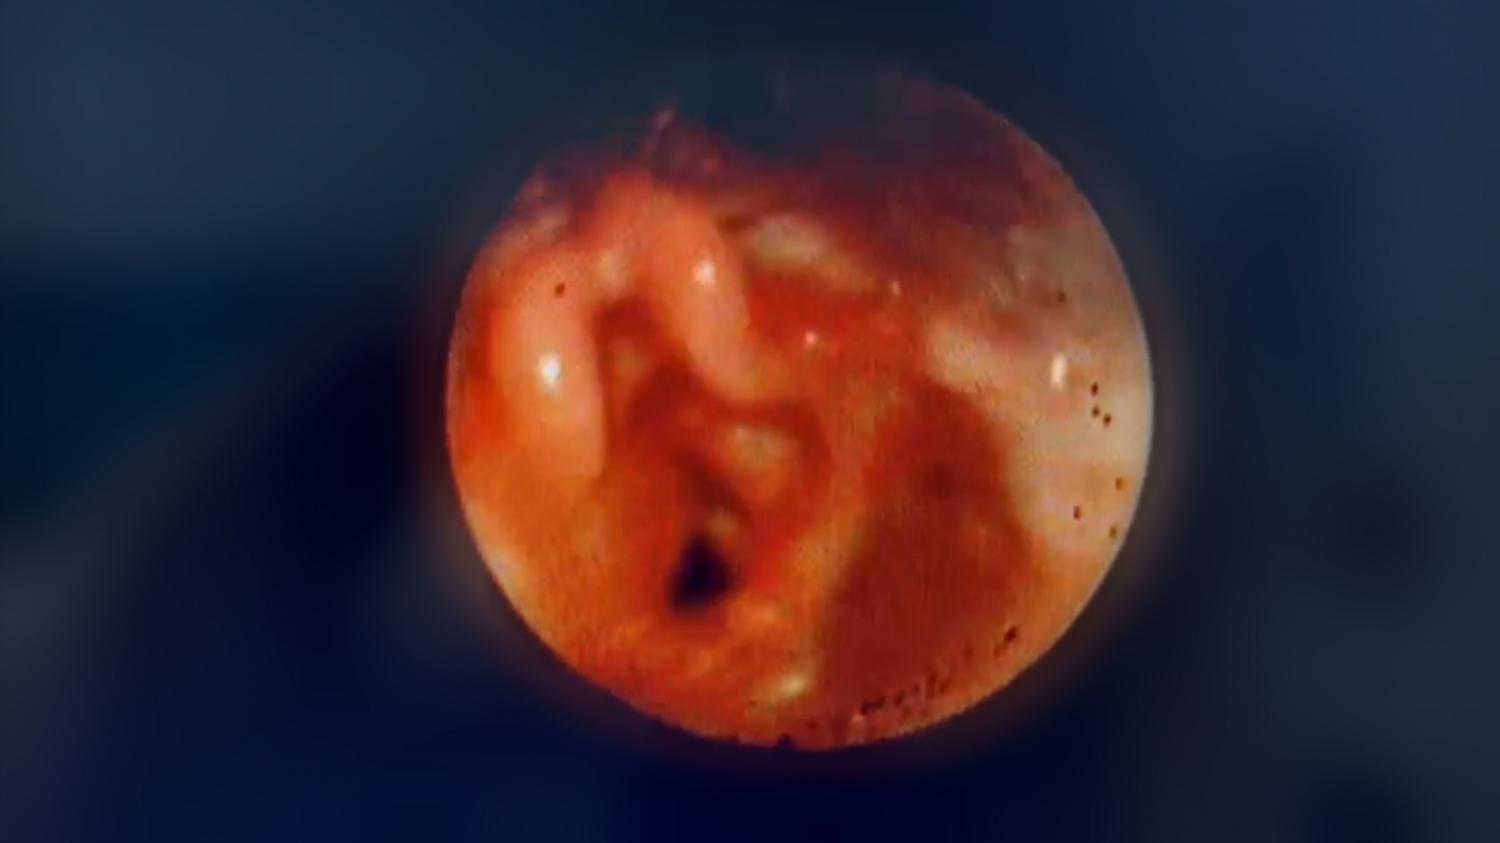

Delfina desde su nacimiento presentó síntomas que alarmaron a su familia, su llanto no era como el de cualquier otro niño, tenía un sonido grave y diferente que fue aumentando progresivamente. Pronto y por medio de una fibroscopía que le practicaron en su provincia de origen, descubrieron que presentaba una obstrucción de la vía aérea alta a causa de la presencia de un quiste dentro de la pared de la laringe, por sobre sus cuerdas vocales.

“Cuando la vi decidí repetir la fibroscopía para cerciorarme del diagnóstico y programamos una microcirugía de laringe bastante complicada, que se realiza completamente por vía endoscópica. Anteriormente, se hacía por cervicotomía, es decir, por medio de una incisión cervical para acceder hasta el quiste, pero actualmente se la realiza por vía endoscópica”.